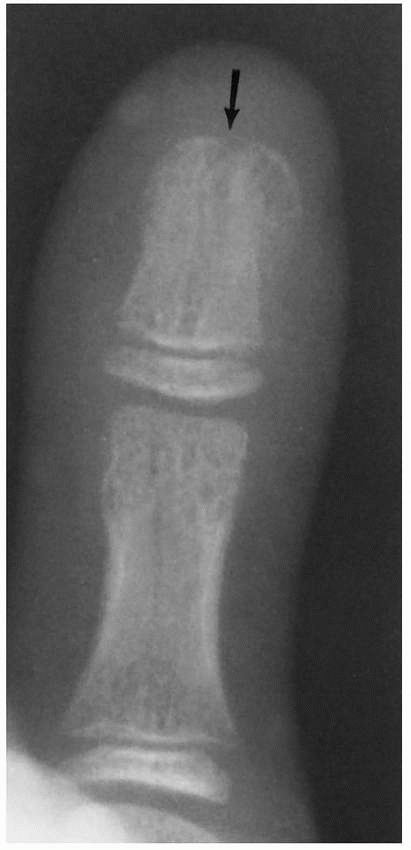

![]() |

FIGURE 8-6 A-C.

A 9-year-old girl with incurving of the tip of the right small finger. Similar findings are noted in family members. The anteroposterior and lateral radiograph shows radial and palmar incurving of the distal phalanx, characteristic of Kirner deformity. |